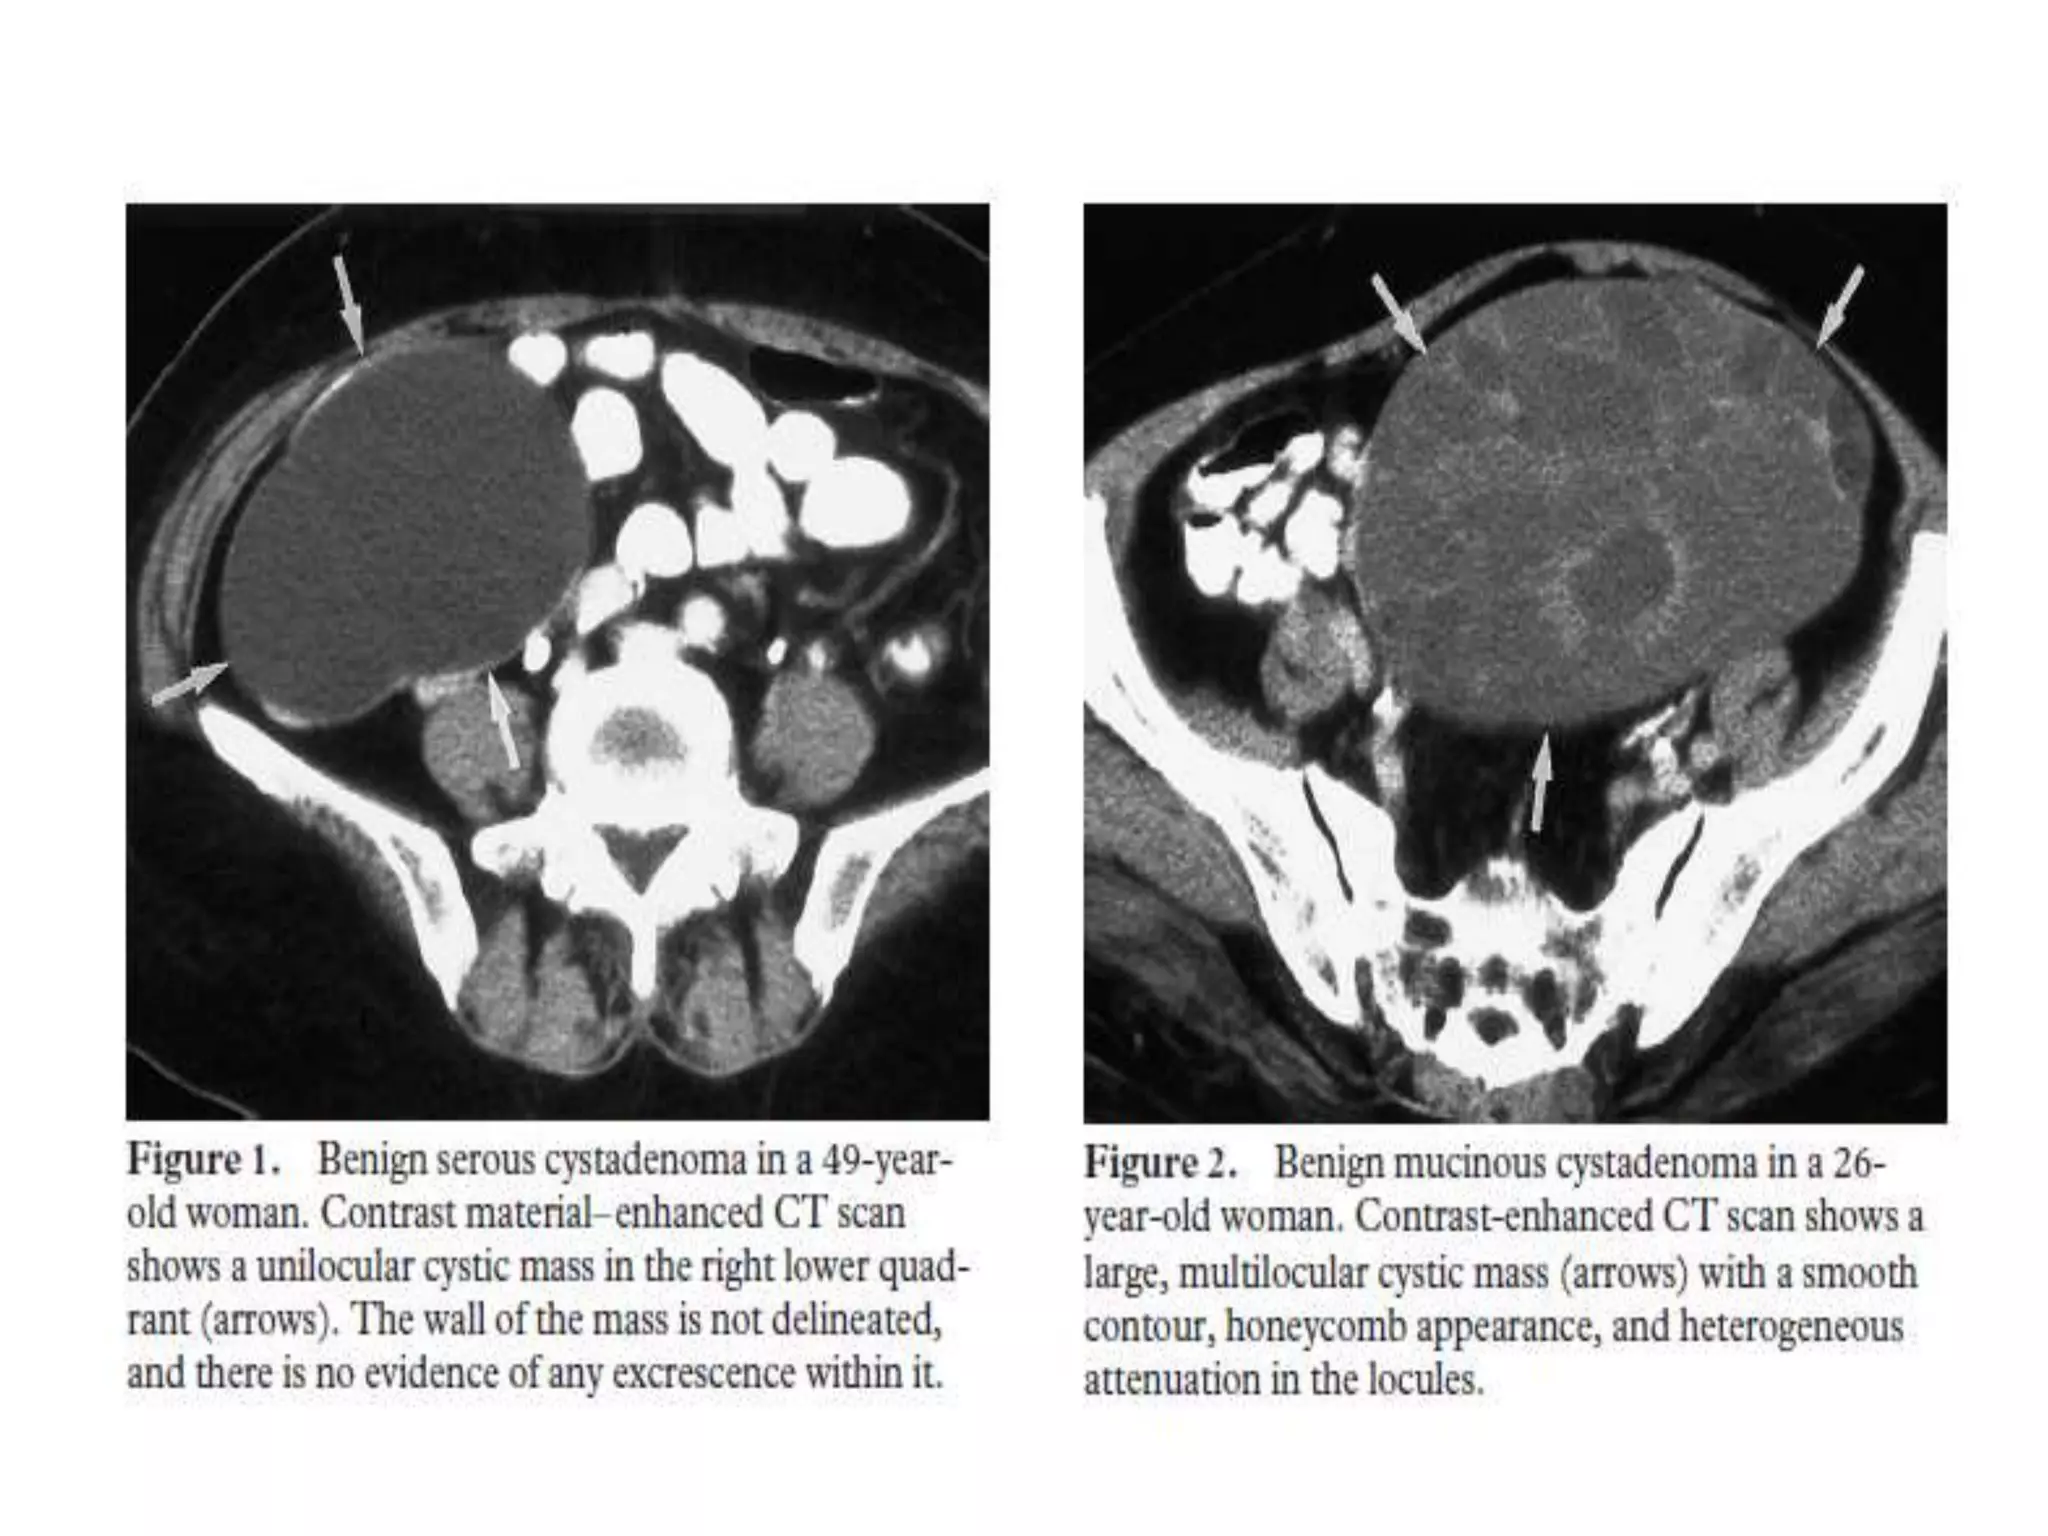

1. Serous cystadenoma is a thin-walled, unilocular or multilocular tumor filled

with serous fluid. This tumor is very common and may mimic a physiologic

cyst or, occasionally, an atypical mature cystic teratoma that lacks the

characteristic eccentric mural nodule.

2. Mucinous cystadenoma is less common, is almost always multilocular, and

may be large. In many of these tumors, the MR imaging and CT

appearance of the individual locules may vary as a result of differences in

degree of hemorrhage or protein content.

Key Imaging Features inDifferential Diagnosis 1. Serous cystadenoma is a thin-walled, unilocular or multilocular tumor filled with serous fluid. This tumor is very common and may mimic a physiologic cyst or, occasionally, an atypical mature cystic teratoma that lacks the characteristic eccentric mural nodule. 2. Mucinous cystadenoma is less common, is almost always multilocular, and may be large. In many of these tumors, the MR imaging and CT appearance of the individual locules may vary as a result of differences in degree of hemorrhage or protein content. 3. Although there is considerable overlap in morphologic characteristics and corresponding imaging features that in many cases prevents definitive preoperative characterization as benign or malignant, features that are suggestive of malignant epithelial tumors include a thick, irregular wall; thick septa; papillary projections; and a large soft-tissue component with necrosis.